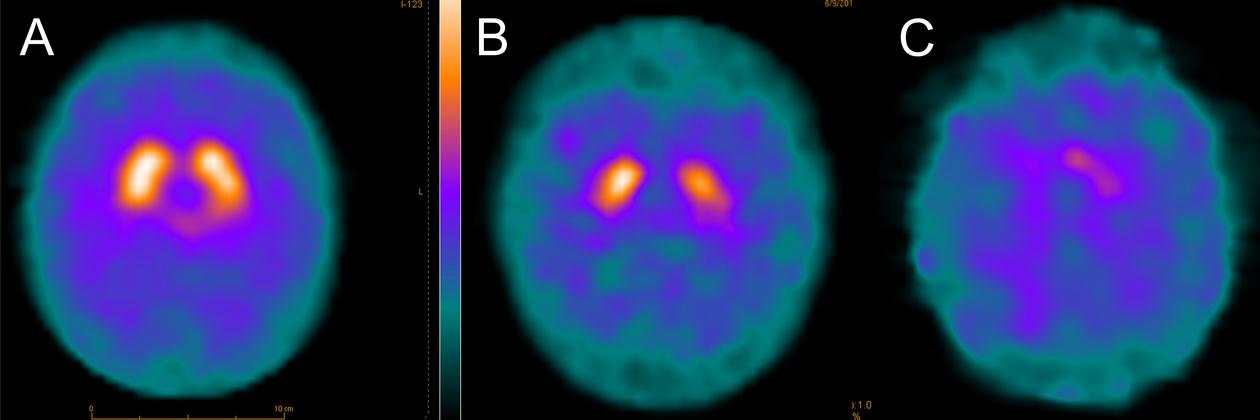

Dopamine transporter (DAT) imaging shows the uptake of a radioactive tracer in the nigrostriatal terminals (bright areas). This reflects the integrity and density of the dopaminergic neurons in the substantia nigra. Patients with POLG mutations (C) have severe nigrostriatal degeneration, which is more pronounced than even in patients with Parkinson's disease (B). The scan of a healthy person (A) is shown for comparison. Tzoulis et al., Brain 2013.